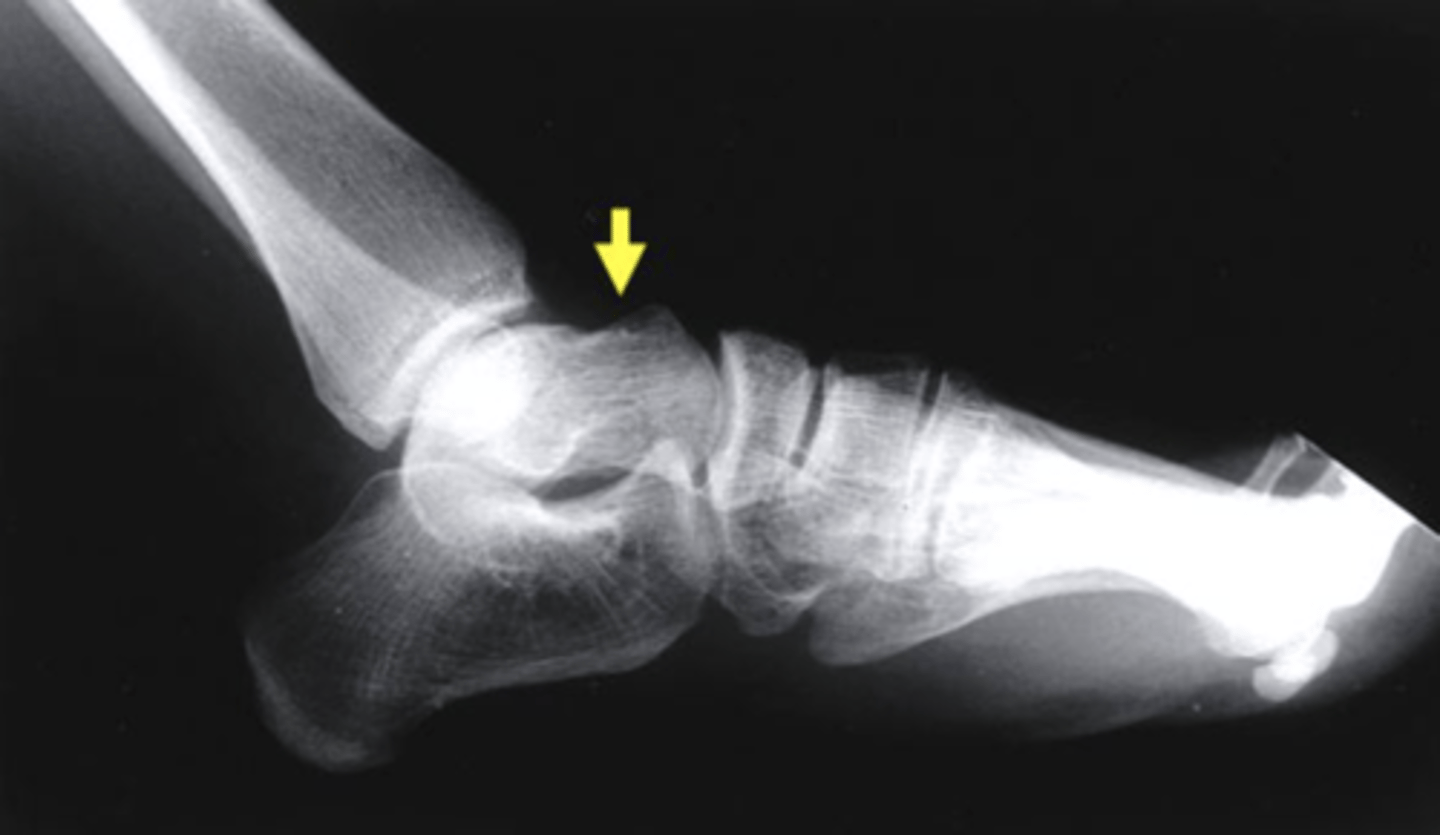

Which structure is highlighted by the yellow arrow?

talus